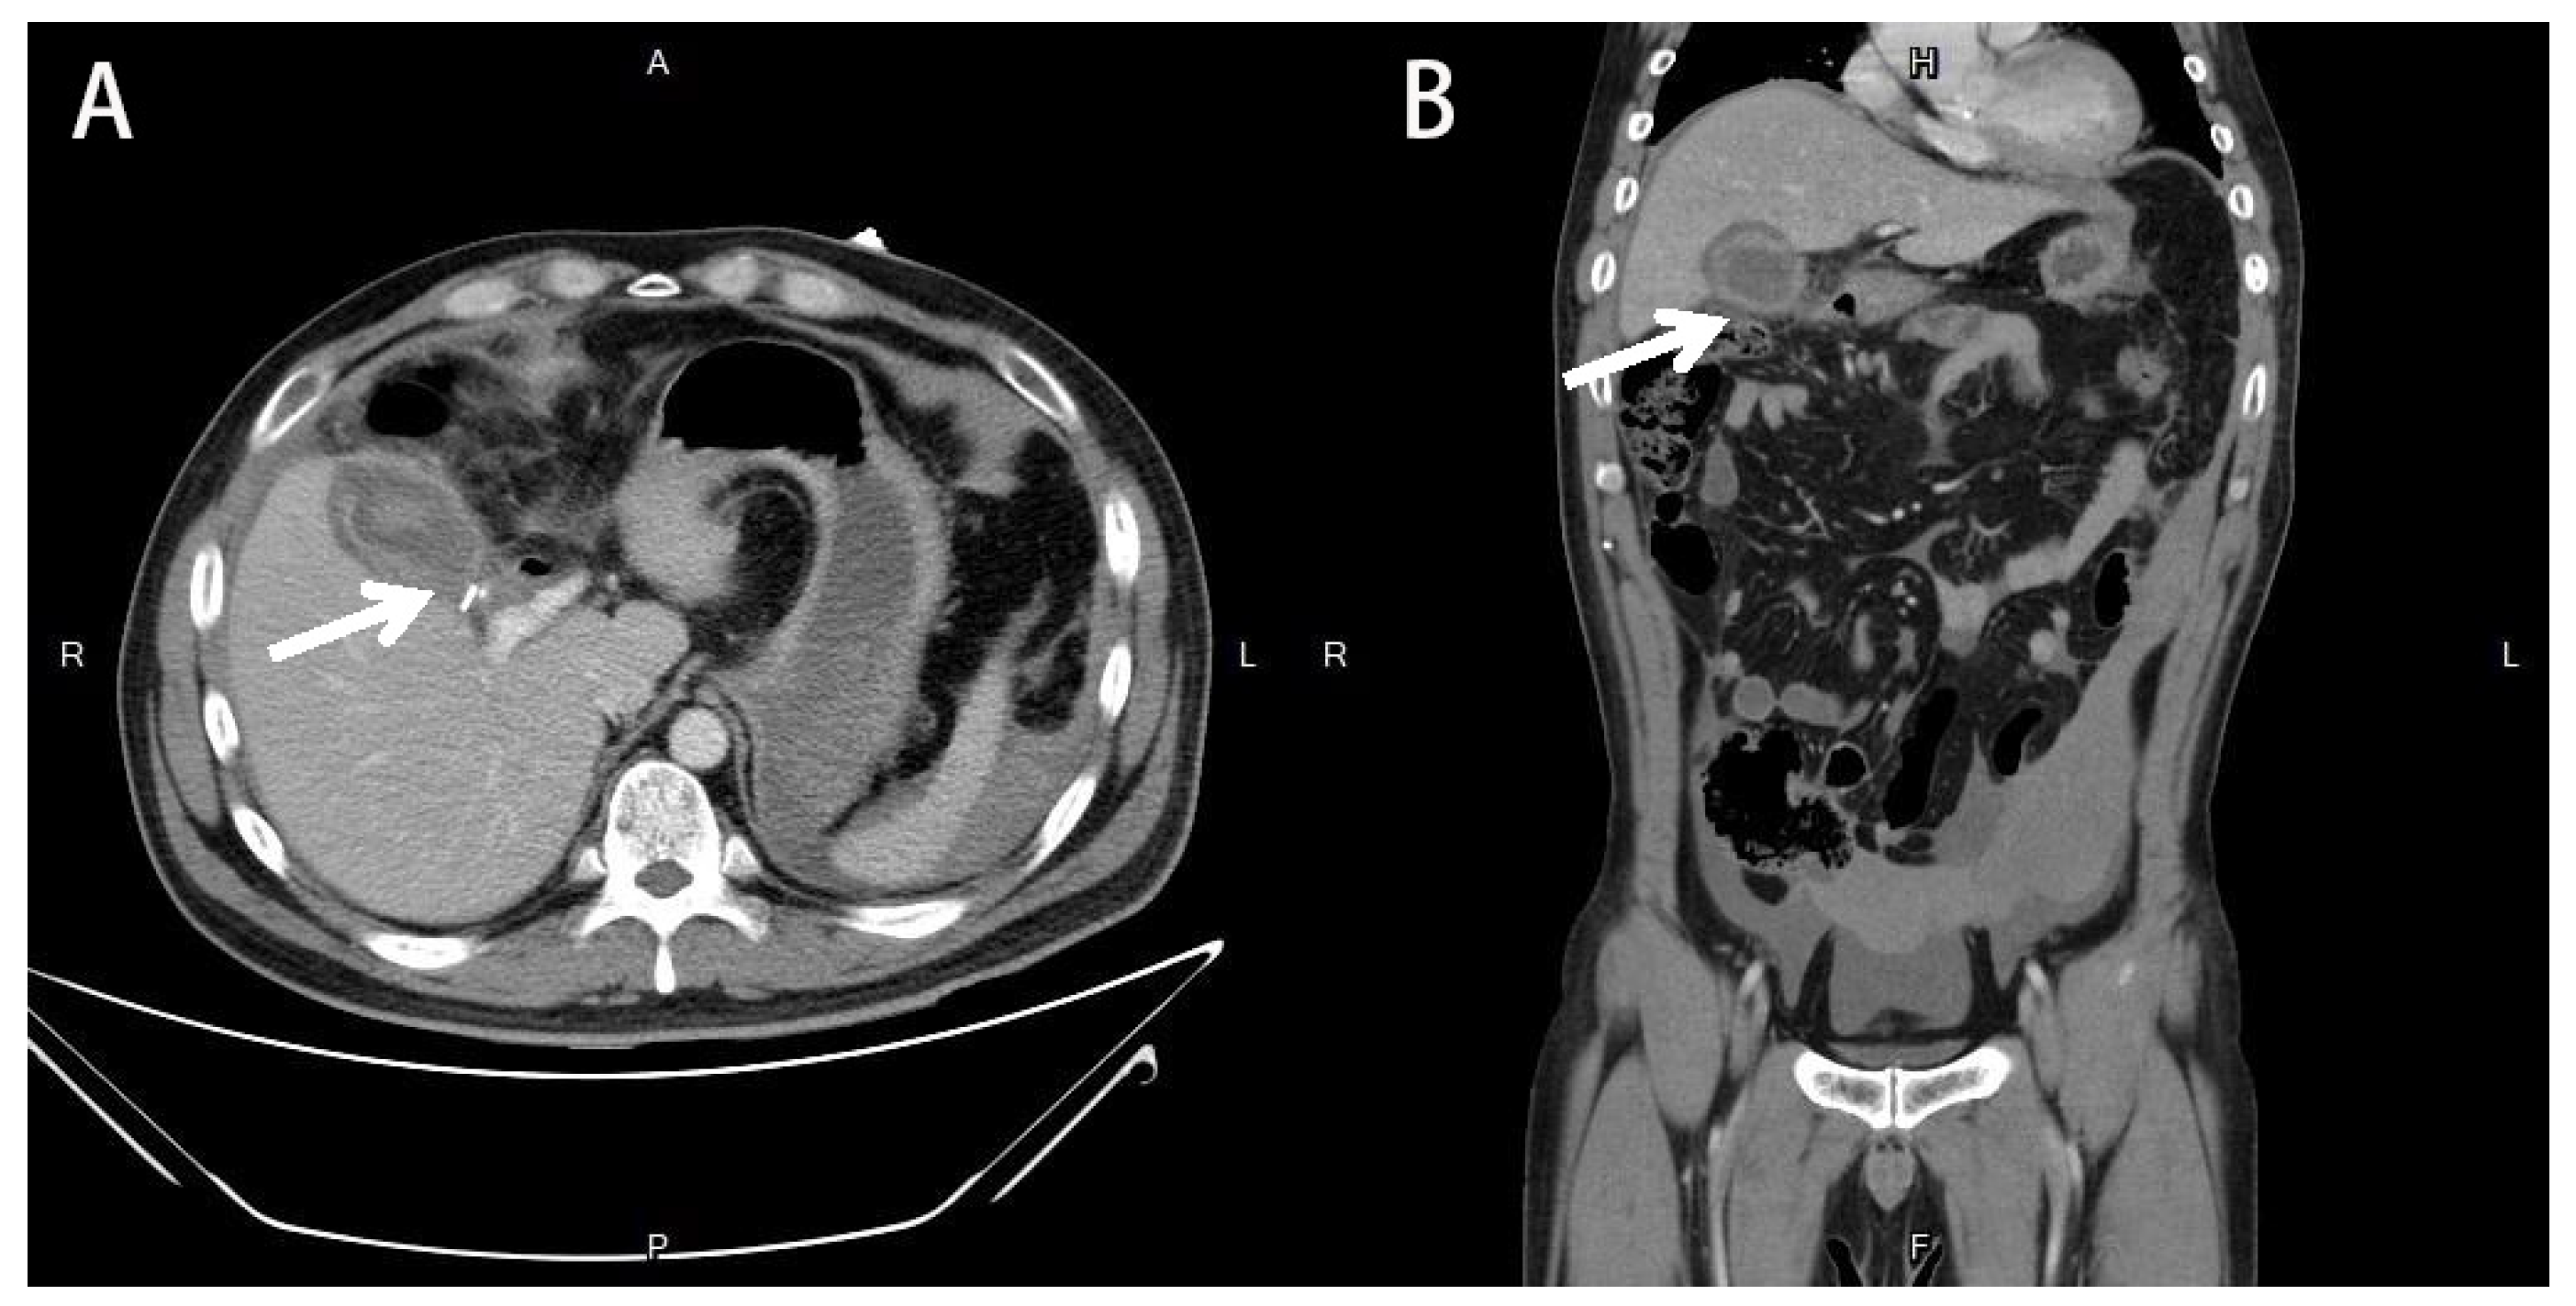

2. Detailed Case Description